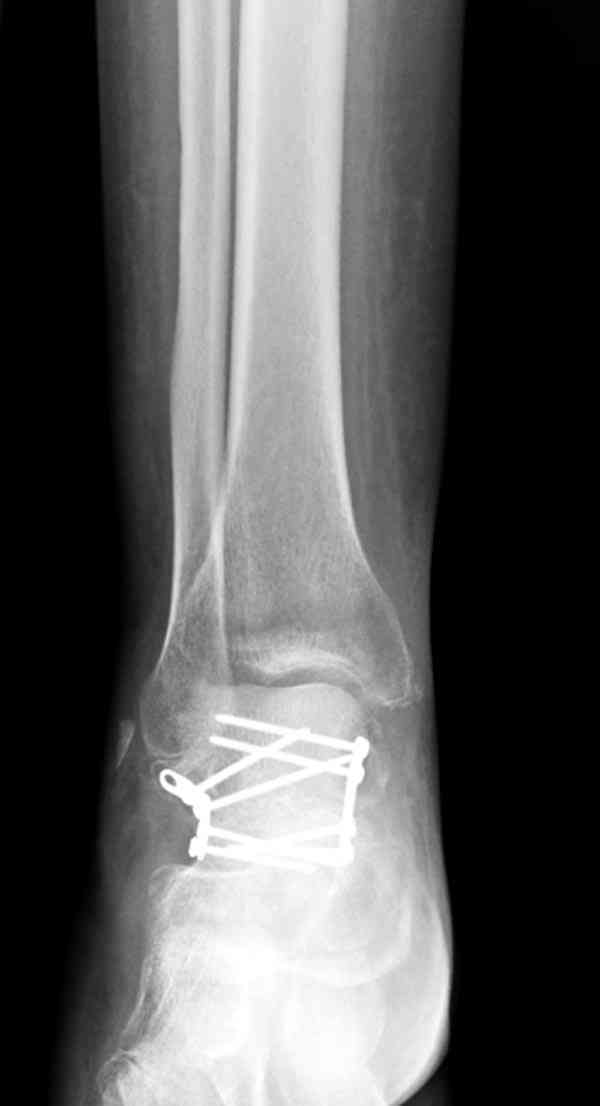

Решили не связываться с остеосинтезом, а сделать сразу берцово-пяточный блок. Снимки в приложении.

По завершении удлинения, наверно, заштифтуем.

Комментарии/критика приветствуются.